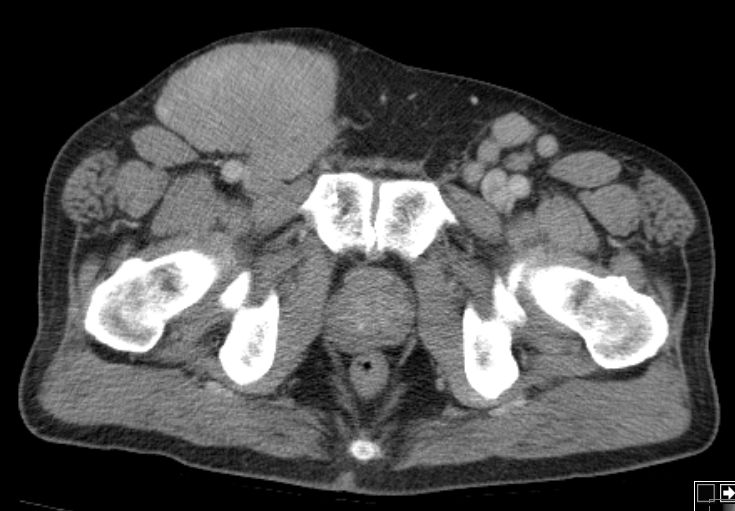

inguinaler Bulk |

72-jähriger Mann mit Verdacht auf

Hernia inguinalis rechts. PE: diffuses großzelliges B-Zellymphom.![]() |

Befall der Nl. iliaca externa![]() | ||